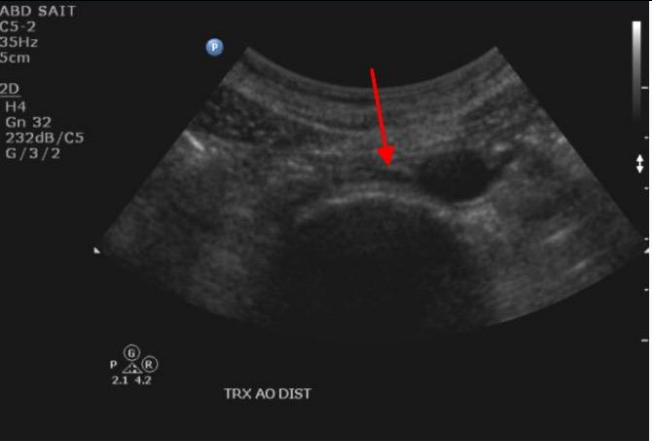

Label the red arrow

Right hepatic vein